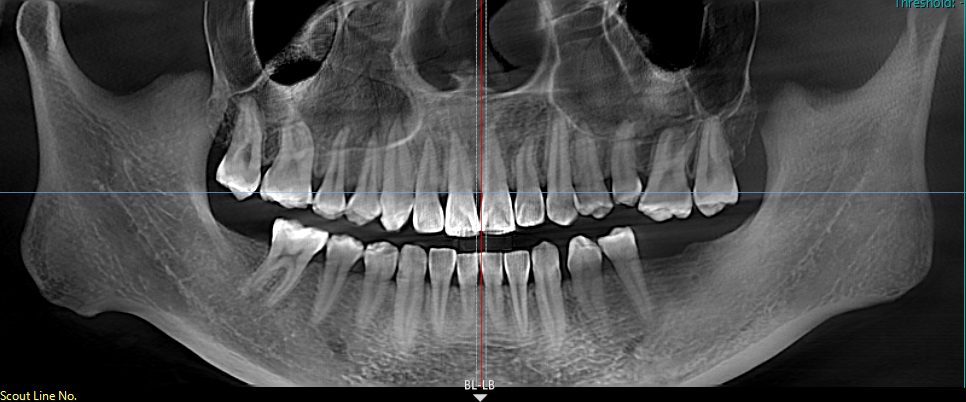

小王右下两颗大牙缺失了两年多,她一直没太在意,直到吃东西越来越费劲,才引起重视来到区中医医院口腔科就诊。易建飞通过CBCT影像检查发现,小王缺失牙齿对应的上颌牙竟然像"疯长的野草"一样伸长了2.3mm!这种情况如果直接种牙,不仅效果不好,还可能导致咬合创伤。

面对此情况,易建飞团队决定采用"正畸-种植联合疗法",先正畸后种植,先改善牙齿排列和咬合关系,为种植牙提供更理想的条件,也为种植牙齿提升美观性、功能性和长期稳定性。这种综合治疗方式能够更好地满足患者的需求,实现更自然、协调的口腔修复效果。

为让患者理解治疗方案,医生耐心解释:"就像盖楼前要先打地基,你的牙齿也需要先“修轨道”,把伸长的牙齿压回去,才能为种牙创造足够的空间。"经过半年的治疗,小王的牙齿不仅重新对齐,种牙后的咬合功能也完全恢复。"现在啃苹果时,两侧牙齿均匀用力的感觉真的太棒了!"她兴奋地说,"以前因为缺牙,我总是不敢大笑,现在终于可以自信地露出笑容了。"

易建飞提醒,后牙缺失超过3个月就需要及时干预,否则可能导致邻牙移位、咬合紊乱等问题。60%的种植失败案例都源于咬合空间不足,而"先正畸后种植"的联合疗法可以有效避免这些问题,甚至减少30%的骨增量需求。